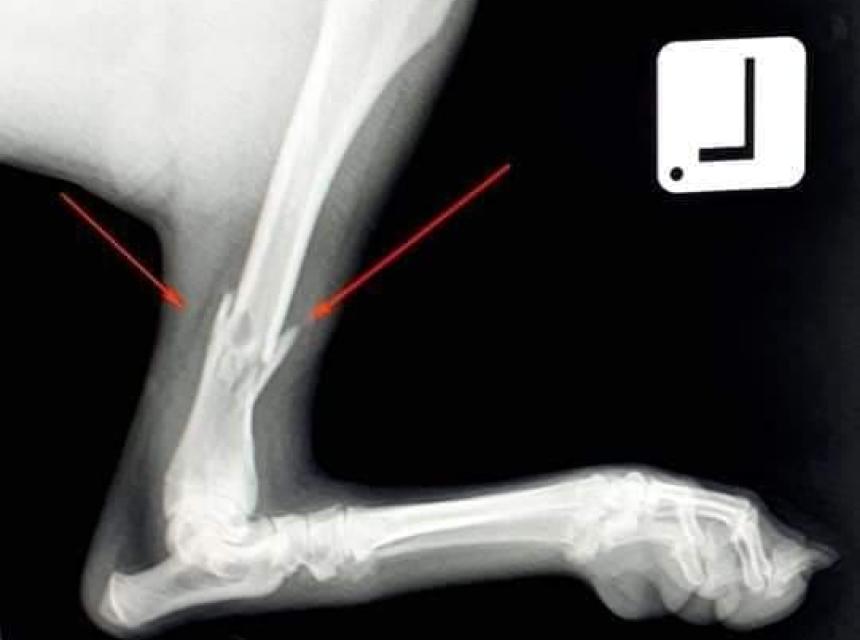

Stigli su i RTG snimci  na osnovu kojih su dijagnosticirane frakture obje butne kosti kao i fraktura tibie.

Ortopedski zahvat jedne noge je predviđen za sutra u saradnji sa Veterinarskom stanicom PET DOC 4U Lukavac, dok će fraktura na drugoj nozi biti sanirana tri dana nakon prvog zahvata.